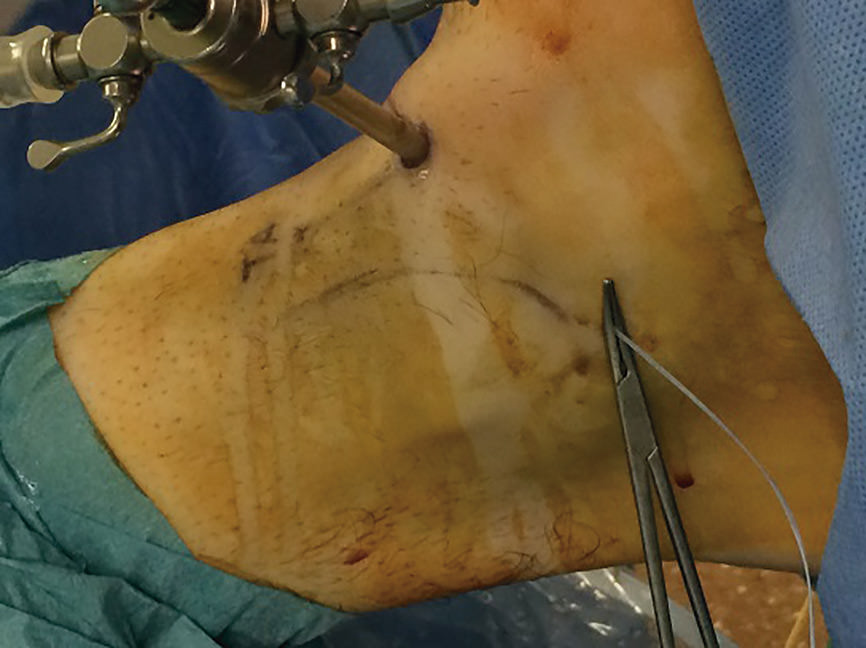

Posteriormente, desde el portal accesorio, con la ayuda de un pasahilos, se pasan los hilos del extremo distal de la plastia a través del pequeño túnel que ha dejado la aguja guía que hemos utilizado para hacer el túnel del astrágalo; de esta manera introducimos la plastia en el túnel del astrágalo y le podemos dar la tensión adecuada en el momento de colocar el tornillo (Figura 7).

El segundo tornillo interferencial de 5 × 15 mm se coloca desde el portal accesorio, con el tobillo en valgo y en neutro de flexoextensión, mientras traccionamos de la sutura para dar la tensión adecuada a la plastia.

Figura 7. Tensado de la plastia con la ayuda de la sutura de la plastia a través del túnel del astrágalo para la colocación del tornillo.